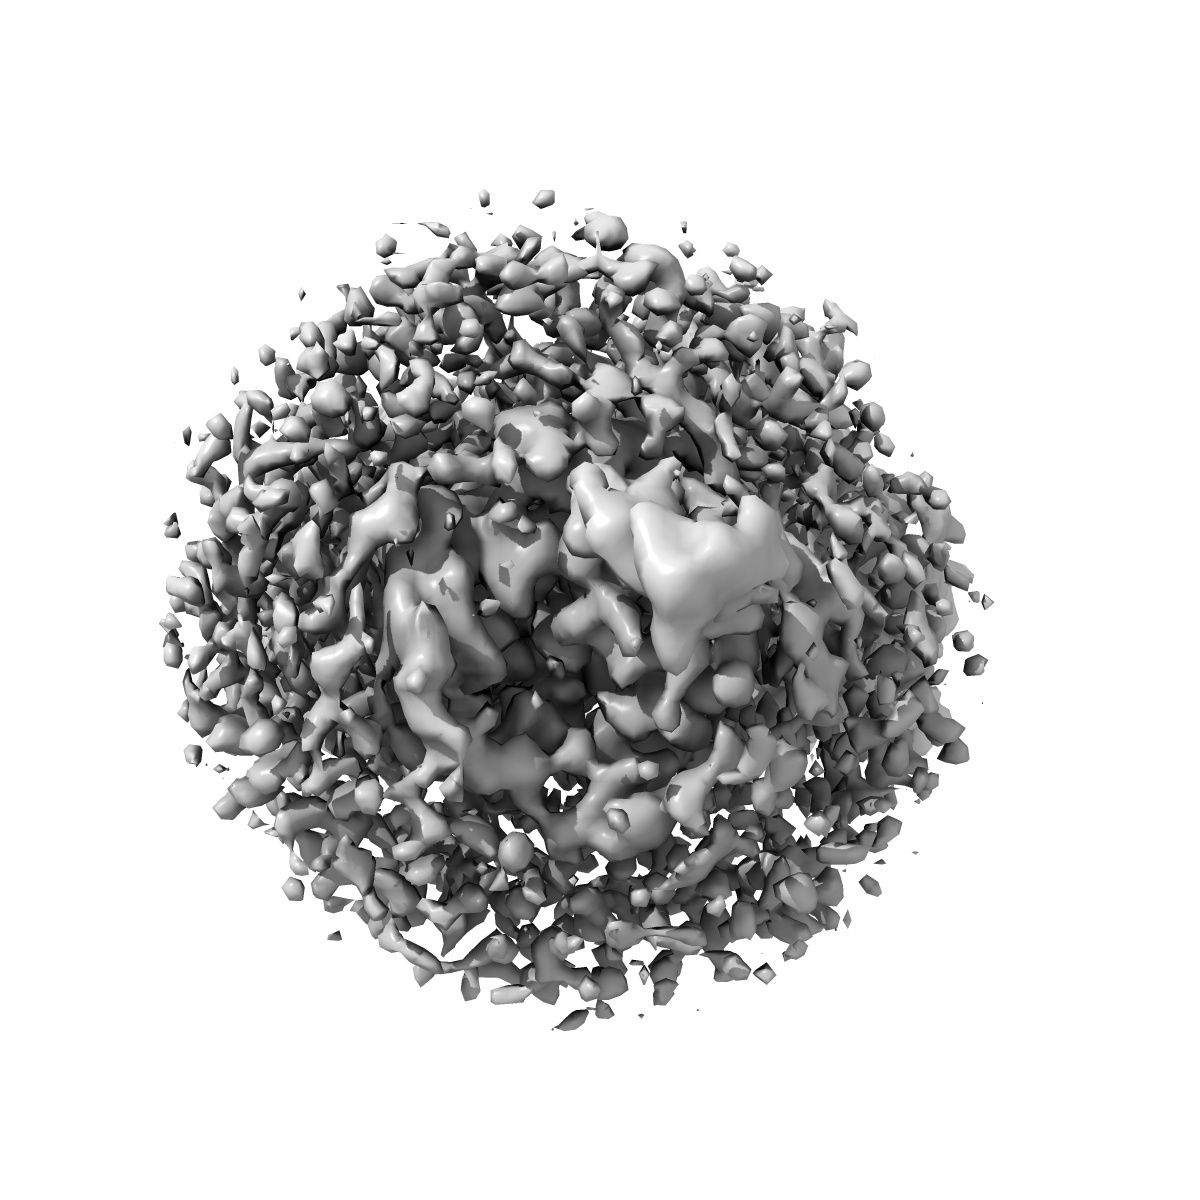

Cryo-EM structure of the human adenosine A1 receptor-Gi2-protein complex bound to its endogenous agonist

Sample: Human adenosine A1 receptor-Gi2-protein complex bound to its endogenous agonist adenosine

Structure of the adenosine-bound human adenosine A1receptor-Gicomplex.

Draper-Joyce CJ , Khoshouei M, Thal DM , Liang YL, Nguyen ATN , Furness SGB , Venugopal H , Baltos JA, Plitzko JM , Danev R, Baumeister W, May LT , Wootten D , Sexton PM , Glukhova A , Christopoulos A

(2018) Nature , 558 , 559 - 563